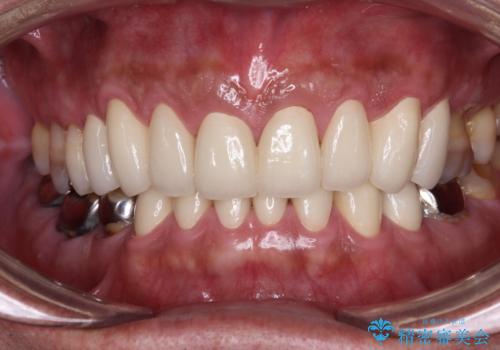

黄ばんだ前歯をきれいに 前歯の審美歯科治療

奥歯の銀歯も気にはなるものの、口を開けたときに目立たないとのことで、上下ともに前歯を中心にオールセラミッククラウンにて補綴治療を行うこととしました。

咬合力が非常に強いため、就寝時には上下ともにマウスピースを使用していただくよう指導をしています。